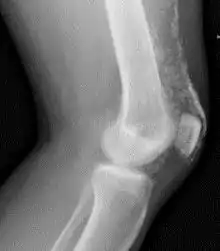

![]() Рентгенограмма коленного сустава пациента с дерматомиозитом. | |